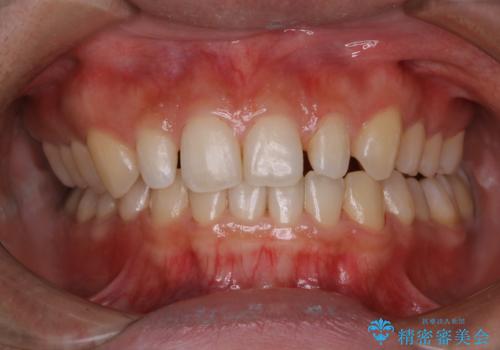

前歯のセラミック製作前にPMTC

- 前歯のすき間をセラミックで治療するため、処置前にクリーニングを希望されました。PMTC30分コースを行いました。

PMTCは、国家資格取得者の歯科衛生士により、専門的な機械や材料を使用してのクリーニングです。一人一人の患者様のお口の状態に合わせたクリーニングを行います。

セラミック治療などの際に歯肉が腫れていたり、治療中に出血したりすると

、精密に型取りができなかったりすることがあります。

PMTCを行うことで、歯肉の引き締まりも期待できます。治療前にもPMTCを行うことはおすすめです。